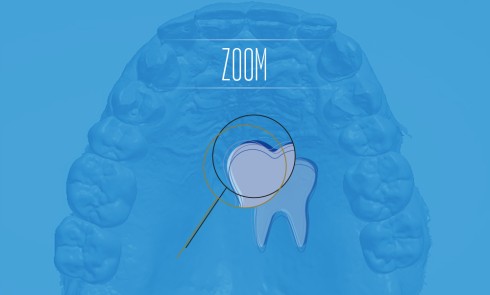

Simple au premier abord (fig. 1), cette situation se révèle souvent complexe après analyse, en particulier au niveau de l’arcade dentée (2).

La plupart du temps, les édentations successives et progressives ont provoqué des versions, rotations et surtout des égressions (fig. 2).